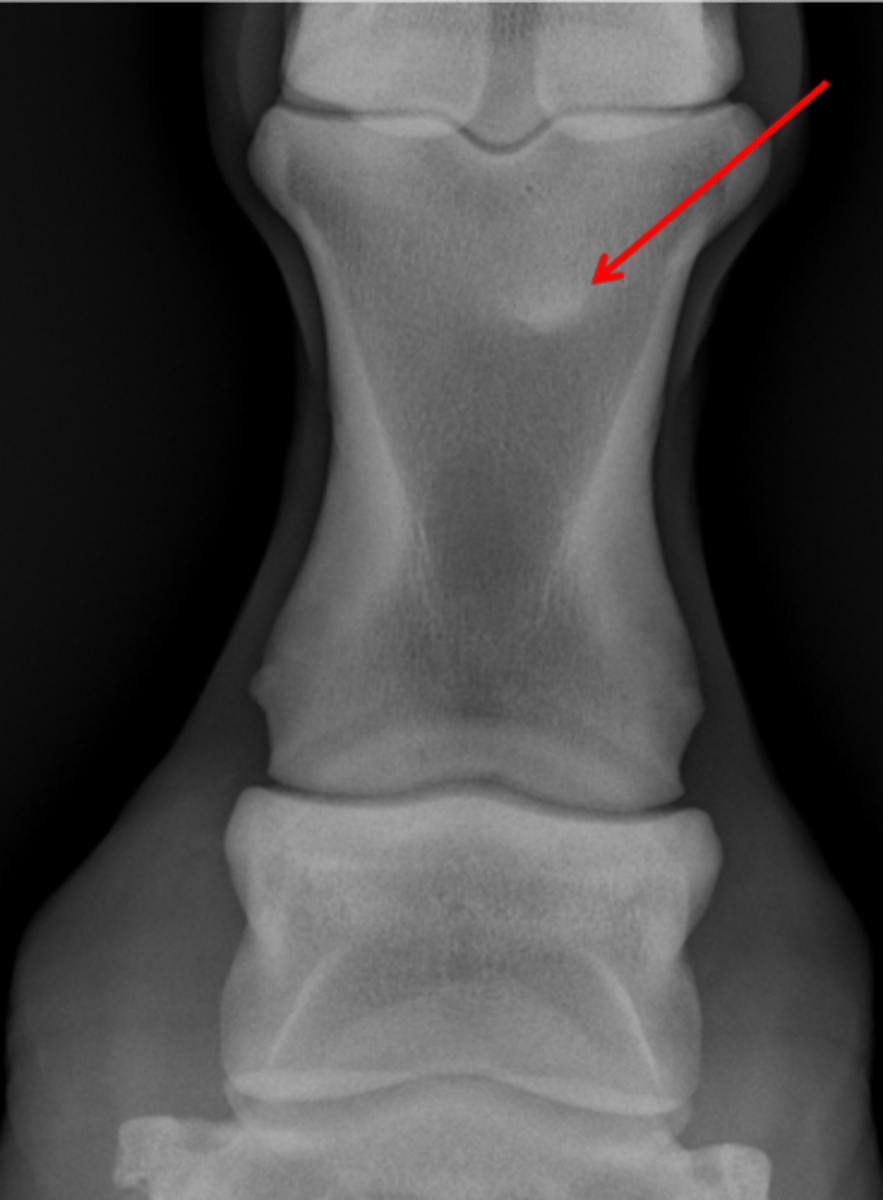

Fetlock joint, DP

ID joint and view

Sagittal ridge

Attachment of collateral ligaments

Proximal sesamoid bones

Condyles of the third metacarpal bone